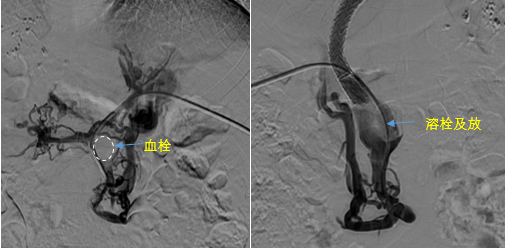

• 血栓攔路,如何破局——罕見巨大門靜脈血栓TIPS手術(shù)實錄

血栓攔路,如何破局——罕見巨大門靜脈血栓TIPS手術(shù)實錄

日前,西安國際醫(yī)學(xué)中心醫(yī)院消化病醫(yī)院為一位罕見巨大門靜脈血栓患者行TIPS手術(shù)。將患者體內(nèi)的“定時炸彈”拆除。9月份的一天,李女士晚飯后發(fā)覺惡心,嘔吐出鮮紅色的血塊,隨即又出現(xiàn)了黑便。在醫(yī)院檢查發(fā)現(xiàn)是食管胃底靜脈曲張破裂出血?!?/p>